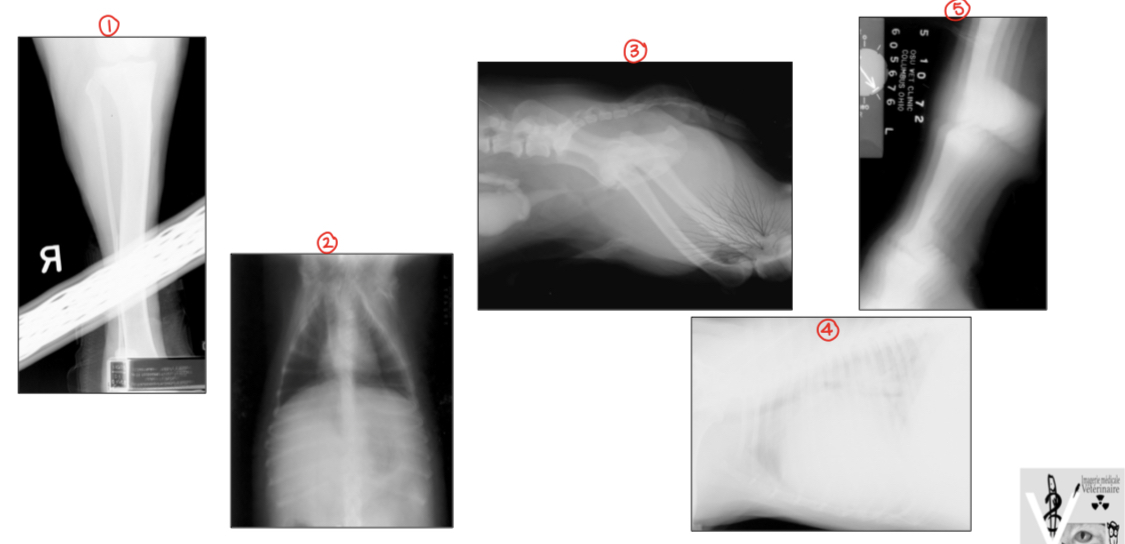

Évaluez la qualité des projections suivantes

A

1) objet qui bloque le faisceau

2) image floue (facteurs d’exposition inadéquats) et projection non collimatée (rx abdo? thorax?)

3) artéfact chambre noire d’électricité statique

4) sous-exposition (Rx blanche)

5) animal en mouvement